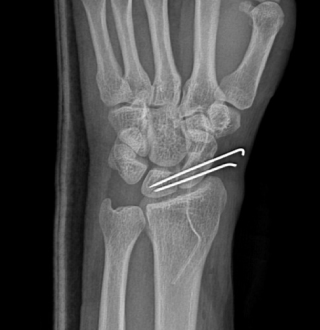

주상월상인대파열

손목 뼈 사이에는 뼈들을 연결하는 내재인대들이 존재하는데, 그 중에서 주상골과 월상골을 연결해주는 인대를 주상월상인대라고 합니다.

주상골과 월상골 사이의 관절면은 서로 협동적으로 움직이는데 여러가지 원인으로 인대 파열되는 질환을 주상월상인대파열이라고 합니다.

주상월상인대파열 진단법

X-ray 진단으로 보이지 않을 경우

→ 초음파, MRI 영상 검사

주상골, 월상골 사이 인대는 아주 작아 MRI 로 진단이 어려운 경우

→ 손목관절 내시경을 통해 진단

힘주지 않았을 때 우측

힘주지 않았을 때 좌측